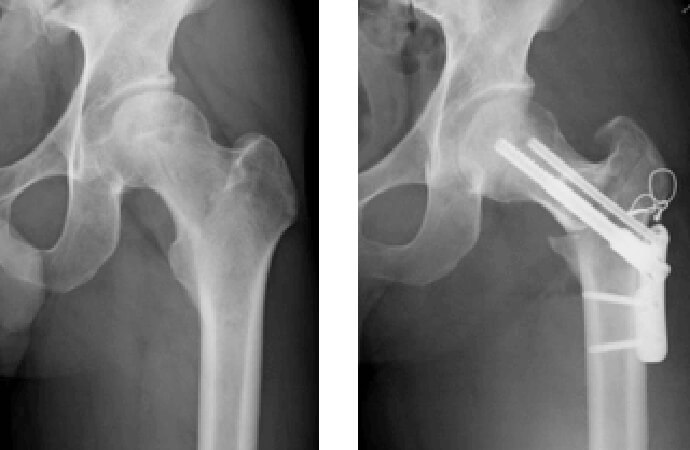

大腿骨偽関節症例

大腿骨転子間骨折症例。複数回手術を行ったが骨癒合が得られず歩行時の疼痛も持続するため当院へ紹介となった症例です。髄内釘の入れ替えおよび自家骨移植を行い、骨癒合が得られ疼痛なく歩行可能となりました。